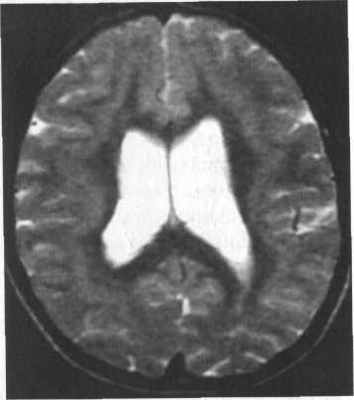

Субкортикальная групповая гетеротопия («двойная кора»):

(а) Аксиальный срез МРТ: широкие, непрерывные группы с таким же сигналом как от коры.

(б) Коронарный срез: в этом же случае имеется расширение желудочков преимущественно спереди.

Кроме того, была проведена магнитно-резонансная томография головного мозга (аппарат Hitachi Airis Mate 0,2 Тесла), согласно которой на аксиальных срезах определялись билатеральные лентовидные зоны, соответствующие серому веществу головного мозга, расположенные преимущественно субкортикально. Изгибы гетеротопированных слоев повторяли основную складчатость кортикальной поверхности. На коронарных срезах подтверждалось субкортикальное расположение гетеротопированных зон. В коре видимых диспластических изменений не отмечено. Таким образом, можно утверждать о наличии у пациентки МР-признаков билатеральной ламинарной гетеротопии серого вещества, что характерно для синдрома «двойной коры» (рис. 2).

Рис. 3.21. Лентовидная гетеротопия. МРТ.

а - IR ИП, аксиальная плоскость; б - Т2-ВИ, аксиальная плоскость.

Полоса гетеротопированного серого вещества отделена

слоем белого вещества от коры и желудочков мозга.